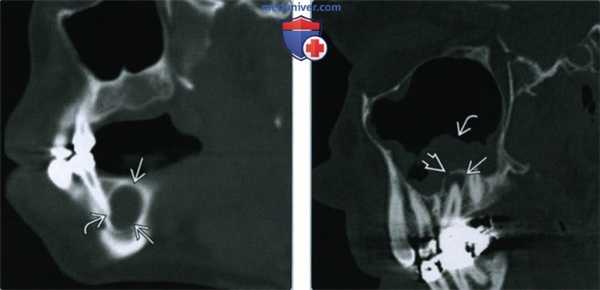

(Слева) На периапикальной рентгенограмме нижней челюсти справа между первым и вторым премоляром (наиболее типичная локализация) определяется боковая периодонтальная киста. Обратите внимание, что киста имеет классический вид слезы.

(Справа) На сагиттальной трехмерной реконструкции (КЛКТ) между первым премоляром и клыком нижней челюсти определяется многокамерное объемное образование. Была выполнена биопсия, подтвердилась гроздевидная одонтогенная киста (ГОК).